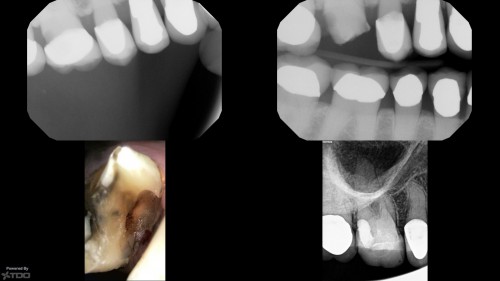

Single visit mindset

By Gary Carr / January 22, 2019

Patient in for a sinus tract check recall today asking questions…… All treatment done by […]